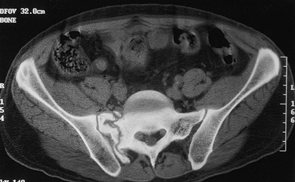

for sacral nonunions, as these cannot be approached safely through the

anterior approach, and it is useful for malunions as well (Fig. 28.15). Sacral malunions or nonunions are an absolute contraindication for the anterior SI joint plate.

![]() |

|

Figure 28.15. Computed tomographic scan illustrating nonunion of the right sacral alae.